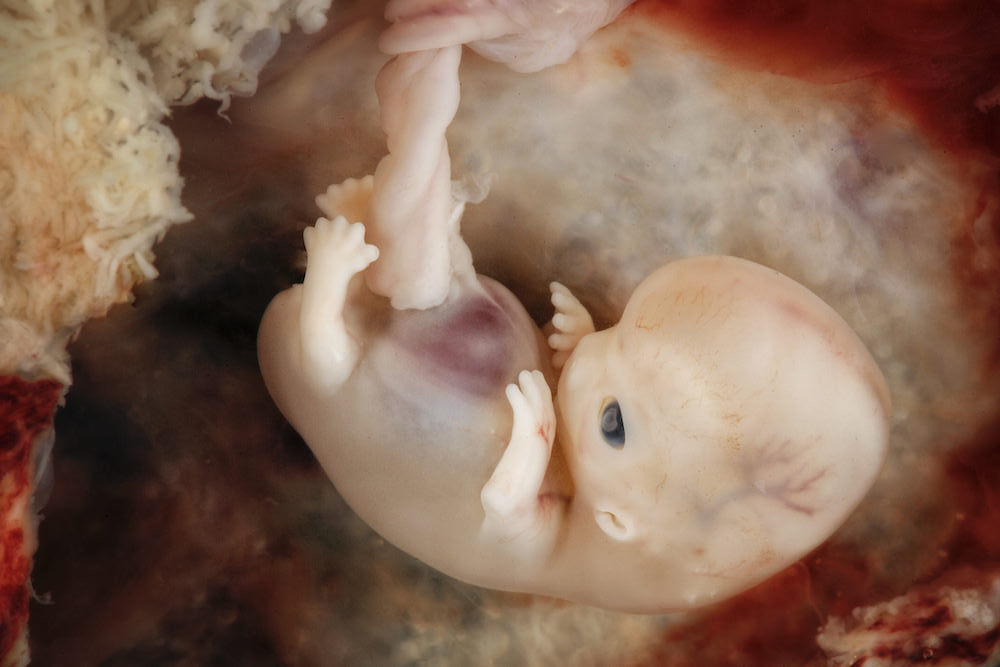

Ein gestaffeltes Lebensrecht?

21. Februar 2021 · Philosophie

Wenn Abtreibungsbefürworter begründen wollen, wieso Abtreibung gut für Frauen oder wenigstens erlaubt sein sollte, kommt unweigerlich das „Zellklumpen“-Argument…